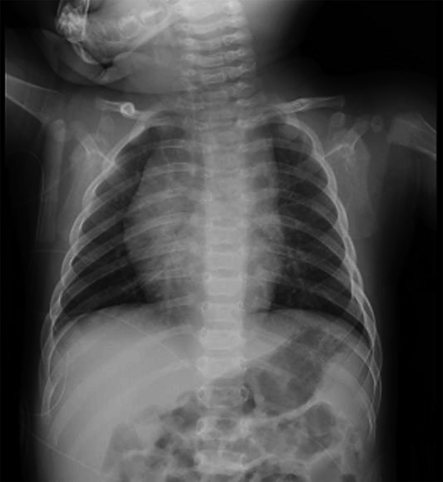

Examination findings on arrival: A simple chest X-ray showed a cardiothoracic ratio (CTR) of 50%, with no evidence of pneumonia or congestion (Fig. 2). Blood tests revealed no particular abnormalities in electrolytes or thyroid function (Table 1).

Fig. 2 Chest X-ray

CTR 50%, no findings of congestion nor consolidation